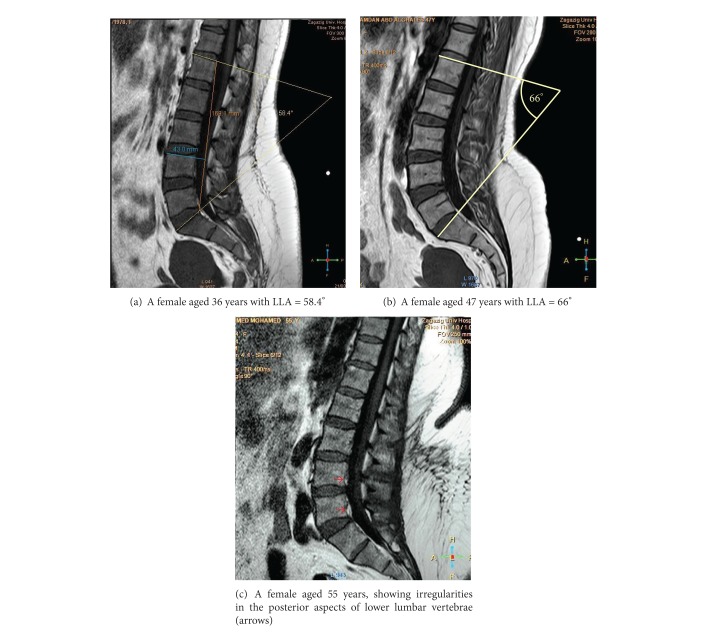

尽管人们越来越认识到腰椎前凸的功能和临床重要性,但对其描述知之甚少,特别是在埃及。与此同时,磁共振成像(MRI)作为一种无创诊断技术已被引入。本研究的目的是利用正中矢状位核磁共振检查腰椎前凸的解剖结构。93例正常腰椎mri(男性46例,女性47例;25-57岁)进行回顾性评价。腰椎曲度及其节段“椎骨和椎间盘”被描述和测量。女性腰椎前凸角(LLA)大于男性。其平均值随年龄增长而增加。男性腰高(LH)高于女性。同时,女性腰宽(LB)高于男性。腰椎指数(LI = LB/LH × 100)性别差异有统计学意义(P < 0.0001)。腰椎前凸是由下腰椎的椎间盘和椎体楔入形成的。总之,MRI可以清楚地显示腰椎前凸的解剖结构。结合LLA使用LI可用于评估腰椎前凸。

Despite the increasing recognition of the functional and clinical importance of lumbar lordosis, little is known about its description, particularly in Egypt. At the same time, magnetic resonance imaging (MRI) has been introduced as a noninvasive diagnostic technique. The aim of this study was to investigate the anatomy of the lumbar lordosis using midsagittal MRIs. Normal lumbar spine MRIs obtained from 93 individuals (46 males, 47 females; 25-57 years old) were evaluated retrospectively. The lumbar spine curvature and its segments "vertebrae and discs" were described and measured. The lumbar lordosis angle (LLA) was larger in females than in males. Its mean values increased by age. The lumbar height (LH) was longer in males than in females. At the same time, the lumbar breadth (LB) was higher in females than in males. Lumbar index (LI = LB/LH × 100) showed significant gender differences (P < 0.0001). Lordosis was formed by wedging of intervertebral discs and bodies of lower lumbar vertebrae. In conclusion, MRI might clearly reveal the anatomy of the lumbar lordosis. Use of LI in association with LLA could be useful in evaluation of lumbar lordosis.